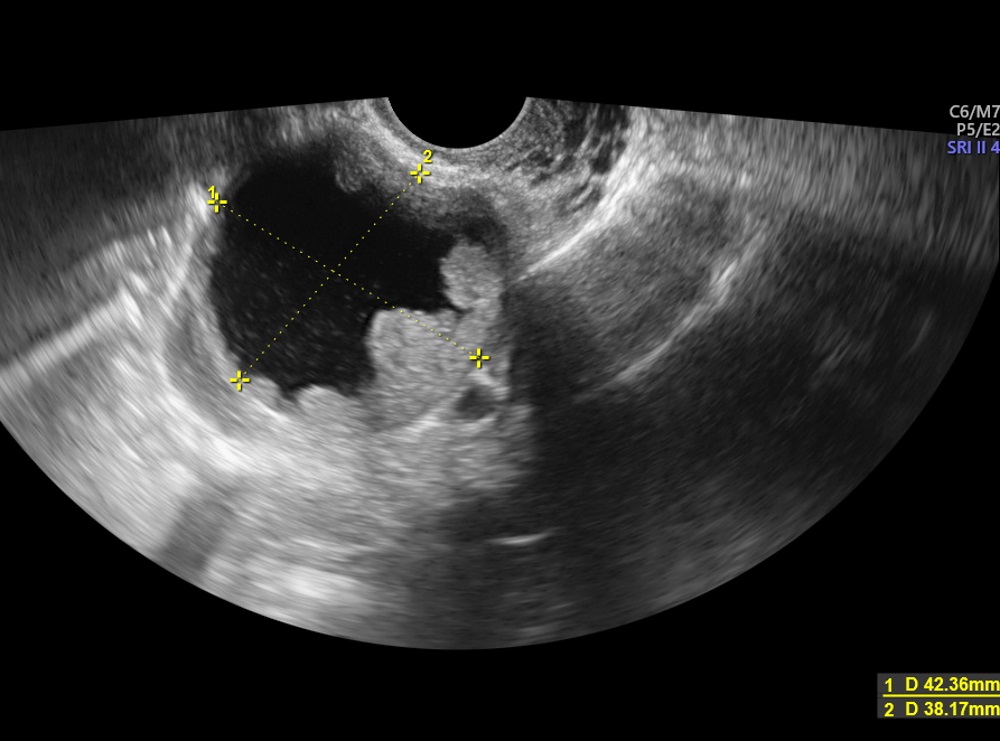

Gunum sonrada asilama olcam 3 ay sonra sizden hamile kalan varmi. Bn de miyom var ama dermoid kisti bilmiyorum 8cm miyomla başladım hamileliğe rahim dışında bulunan subseroz miyomdu 5 haftalıkken düşük tehlikesi yarattı 2 hafta kanamalı bir süreç geçirdim 23 haftalıkken de erken doğum tehlikesi yarattı gap serum ötelettik doğumu şuan 30 haftalık olduk. Bu kist ağrılı birlikteliğe ağrılı mens dönemine kısırlığa yapışıklığa neden olabiliyor. Dr gördü 1 ay sonra 44.

Kisti olup hamile kalanlar. çikolata kisti olup sol tüpü kapalı hamile kalanlar çikolata kisti. Bunun opere olması şart değil. şubatta kontrolüm var dua ediyorum o zamana kadar hamile kalayım diye teşekkür ederim geçmiş olsun size de dermoid kistler ilaçla küçülmüyor maalesef benim de ilk dr görmemişti kisti alttan ultrasonla bakmasına rağmen 2.

Kizlar ankarada 2 devlet kadindogum hastanesi gezdim ama beni mahvettiler. çikolata kisti olup sol tüpü kapalı hamile kalanlar çikolata kisti. Merhaba kistler türüne göre gebe kalmada sıkıntı yaratır çikolata kisti de hamile kalmaya engel olan kistler den biri. Kistimin polikist oldugunu adet gorunce gectigini soylediler ve suan 2 yillik evliyim ozel hastane adini cok duydugum hulisi bulent zeynelogluna gittim dermoid kistimin oldugunu soyledi ameliyat oldum bugun 3.